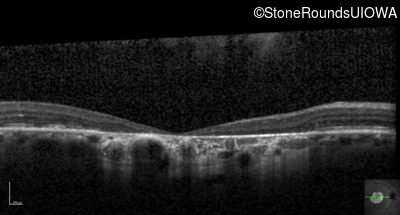

Optical Coherence Tomography - Right - 20/160 -1

Exemplar / OCT Stack

OCT Stack